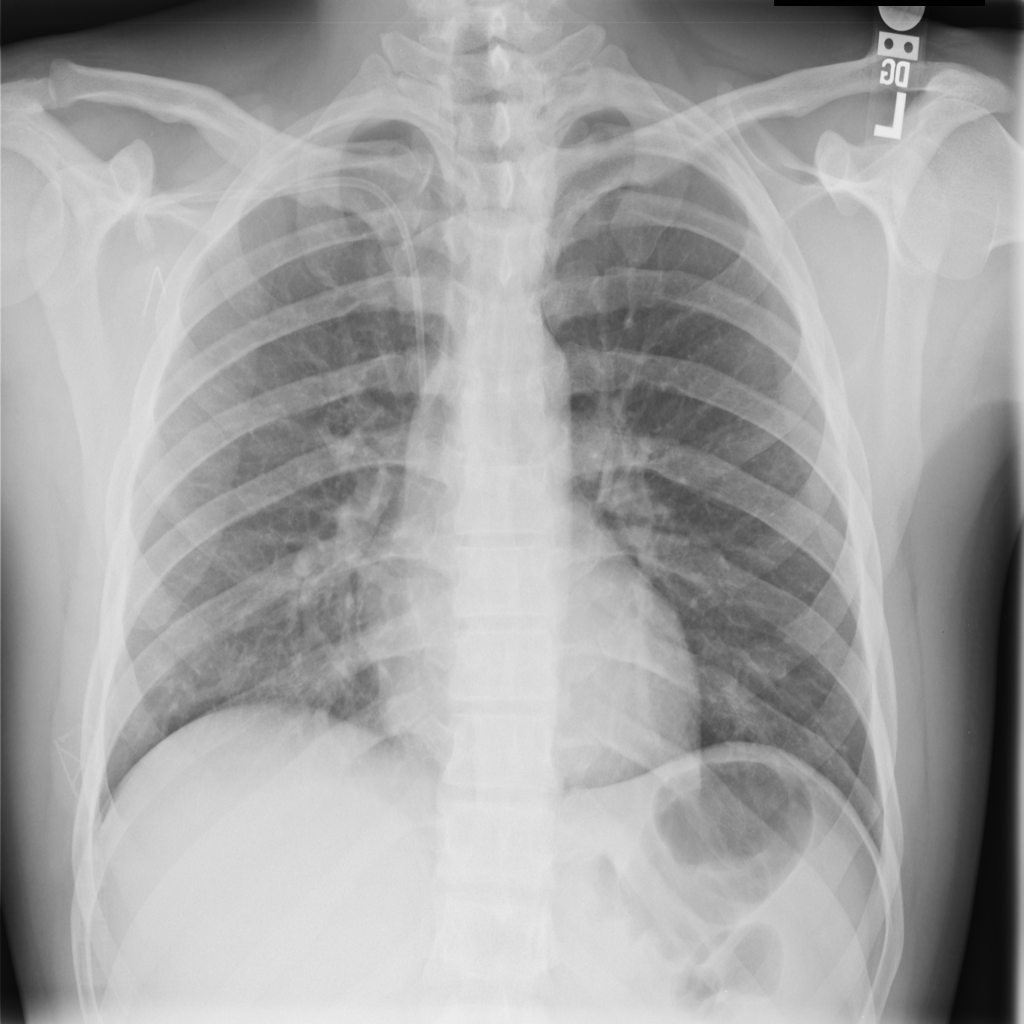

Pneumonia

Pneumonia is an infection of the lung tissue, often caused by bacteria, viruses, or less commonly fungi. On chest X-ray it can appear as focal or patchy air-space opacity, though imaging alone does not always prove the cause.

Showing up to 90 reference images for Pneumonia.

PAT-A1E2 · IMG-001Pneumonia

PAT-A1E2 · IMG-001

AP